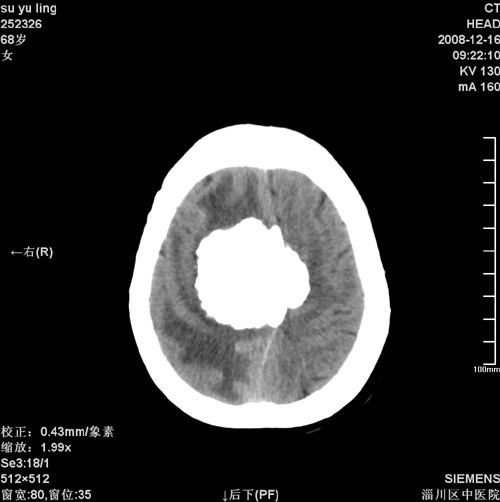

女,68岁,左侧肢体活动不利。

病灶比较均匀钙化,水肿明显,紧贴颅顶与大脑镰并跨越大脑镰----支持脑膜瘤

1)考虑镰旁脑膜瘤钙化。2)小脑萎缩。

头一次看到这么大钙化脑膜瘤,且其周水肿范围太大